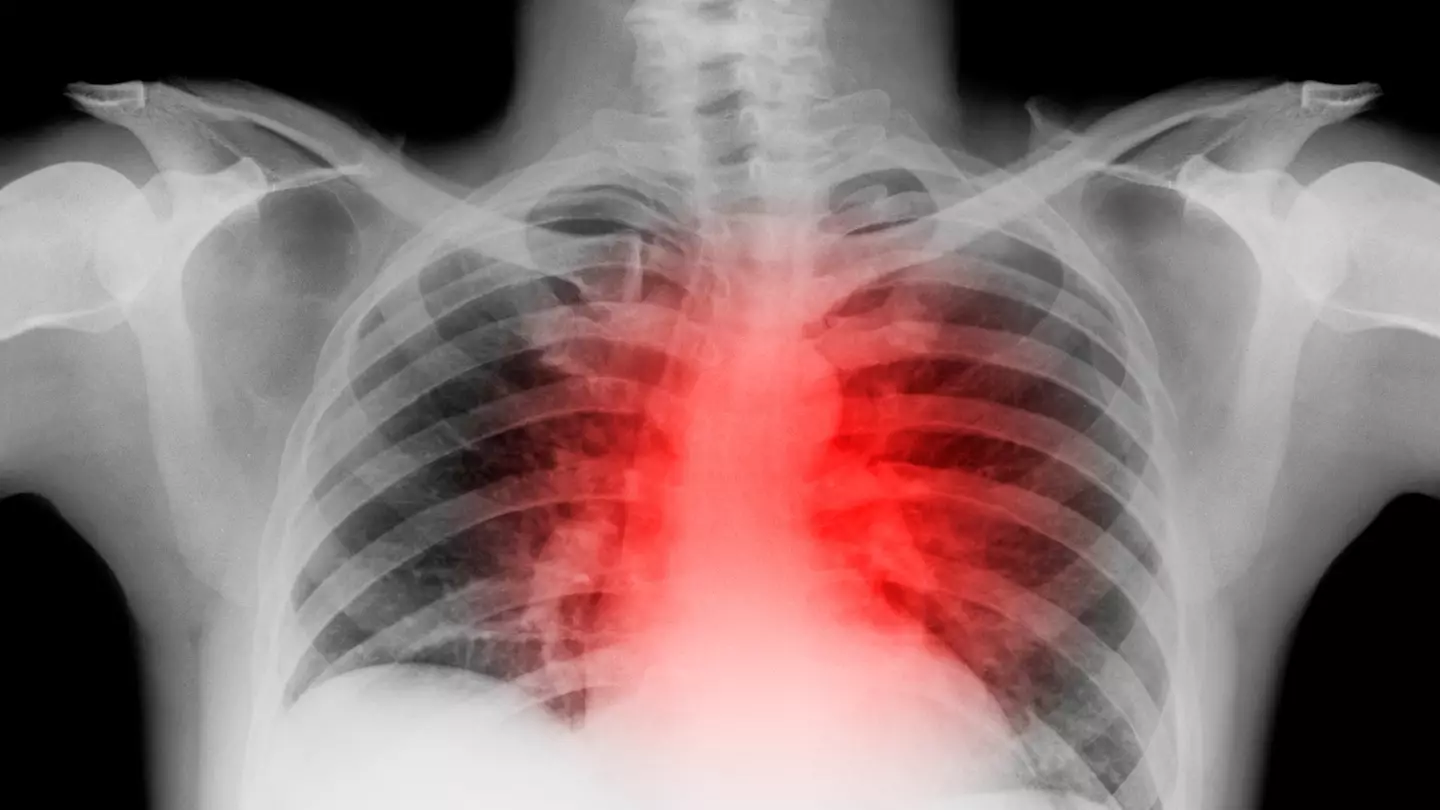

The disease is an aortic aneurysm, and they can be fatal. It is a bulge of the aorta, the largest blood vessel in the human body, that carries oxygenated blood away from the heart to the rest of the body.

An aortic aneurysm is a bulge in the aorta and there are two main types, based on their location along the aorta.

The artery is located in the chest and abdomen, originating in the heart’s ventricle and extending upwards, forming an arch in the chest which descends through the chest and abdomen and into the abdomen.

An aneurysm is a bulge or ballooning in the wall of a blood vessel which can rupture that leads to bleeding. Thoracic aneurysms usually refer to aneurysms located in the chest, and abdominal aortic aneurysms (AAA) refer to the part of the aorta that runs towards the abdomen.